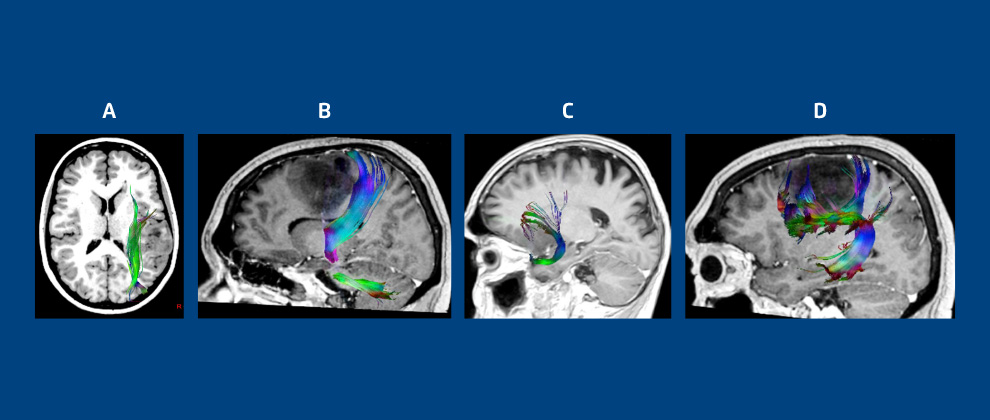

Figura 4: quadros A, B, C e D representam imagens de Tractografia Seletiva.

O quadro A, em Tractografia, mostra relação de lesão tumoral com o fascículo longitudinal inferior; quadro B, em reconstrução do trato corticoespinhal deslocado posteriormente por lesão tumoral; quadro C, em radiação frontal do fascículo uncinado deslocada superiormente por efeito de massa de lesão no opérculo fontal; o quadro D, em segmento frontal e parietal do fascículo arqueado deslocado inferiormente por tumor cerebral frontal.